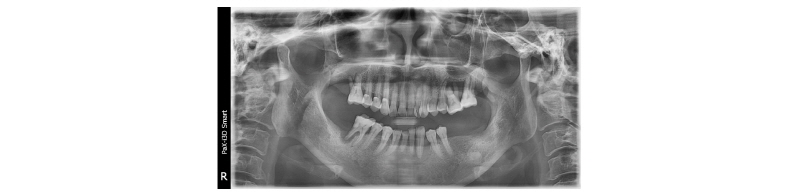

본 59세 여환은 양쪽 위, 아래 큰 어금니가 흔들리고 잇몸이 부었으며 왼쪽 아래 큰 어금니는 오랫동안 없었다는 주소로 본원에 내원하여 임상 및 방사선학적 검진 결과 아래와 같이 관찰되었다. #33 치아는 Mob (+++) Per (+)와 bone loss, #16, 26, 46 치아는 Mob (++/+++) Per (+)와 bone loss, #36, 37 치아는 missing 상태였다. 이에 #16, 26, 33, 46 치아는 hopeless teeth, #17, 36, 37, 47 치아는 missing teeth로 진단되었다(Fig. 19). #16, 26, 33, 46 치아는 발치 후, #i16, i17, i26, i33, i36, i37, i46, i47에 implant 식립과 #i16, i17, i26에 sinus lifting 및 #i33, i46, i47에 GBR을 계획하였다. #i36, i37은 flapless implant surgery 및 immediate loading을 계획하였다. #16, 26, 33, 46 치아를 발치하였고, 2개월 후에, 상, 하 rubber impression 채득 후, stone model 제작하였다. 또한 arch 전용 tray를 bite한 상태로(Fig. 20, 21) CBCT 촬영을 하였다(PHT-30LFO, VATECH). 이후 CBCT 영상과 alveolar ridge와 soft tissue model을 scanning한 영상(TRANSFORMER, Megagen)을 정합하였다. 새로운 영상을 바탕으로 #i36, i37 위치에 implant fixture 식립과 customized abutment와 provisional bridge를 design하였다(R2GATETM, Megagen, Fig. 22, 23). Design대로 3D printer (Perfactory Digital Dental Printer 3, EnvisionTEC) 통해 surgical guide를 제작하였고(Fig. 24) milling machine (TicamPro and WhitecamPro, Megagen)으로 customized abutment와 provisional bridge를 milling하였다(Fig. 28). 임플란트 수술은 5회에 걸쳐서 진행하기로 하였다. 첫 번째 수술일에는 #i36, i37 fixture 식립과 동시에 abutment 체결과 provisional bridge를 합착하였다(Fig. 25-27, 29). 이후, 1개월 후에 #i16, i17 fixture 식립과 lateral approach로써 sinus lifting을 시술하였다. 3개월 후에 #i36, i37에 최종 인상 채득하여 도재금관 수복을 하였다(Fig. 30, 31). 향후 남은 부위에 임플란트 수술 및 보철 진행 예정이다.

Fig. 19. Panoramic view before treatment. |

Ju Whan Lee : Computer-guided Flapless Implant Surgery and Immediate Loading with Customized Restoration, Comparing and Reviewing Error of Guided Surgery. Implantology 2017 |